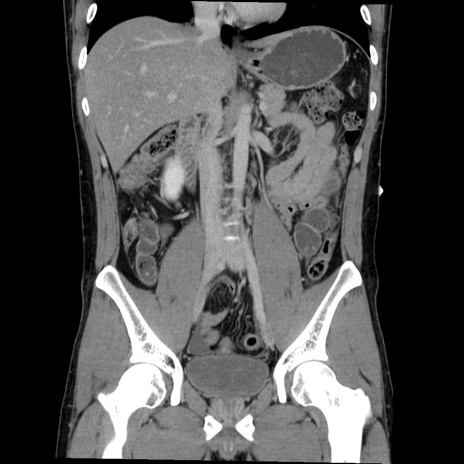

症例36(冠状断像)

【症例】20歳代 男性

【主訴】心窩部痛

【現病歴】今朝より上腹部痛あり。一旦軽快していたが再度出現したため救急要請。昨日夕に白身の魚を含む刺身を食べた。

【身体所見】BP 136/89mmHg、HR 74/min、BT 37.0℃、腹部:膨満、軟、心窩部に圧痛あり。反跳痛なし、筋性防御なし、腸雑音やや亢進あり。

【データ】WBC 17700、CRP 0.48